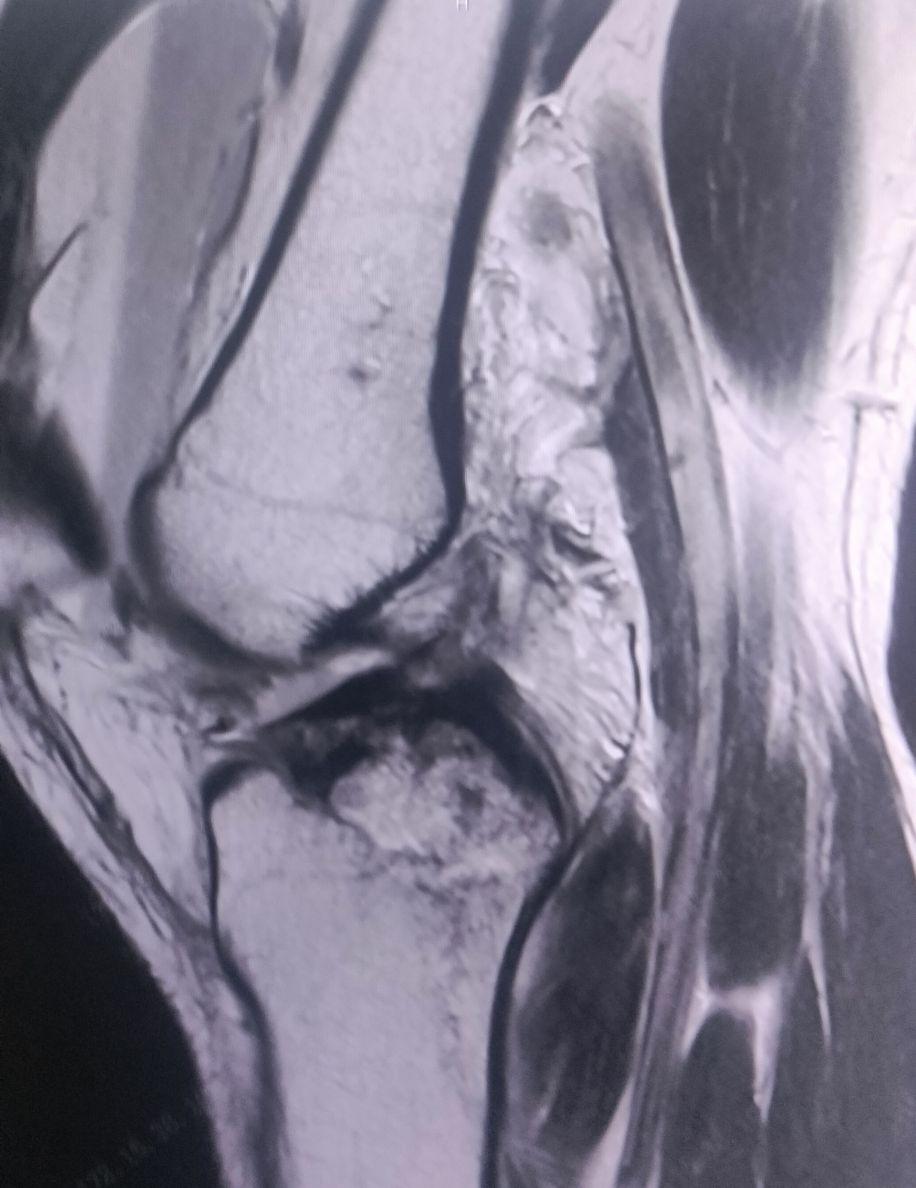

膝关节MR:1.右胫骨近端骨折。2.右股骨远端、腓骨近端异常信号,考虑骨挫伤,不除外骨折可能,结合临床及相关检查。3.右膝前交叉韧带、外侧副韧带局部信号增高,考虑损伤。4.右膝外侧半月板前角变性或损伤。5.右膝关节腔积液,膝关节周围皮下软组织挫伤改变。

该患者少年女性,有外伤史,右膝肿痛、活动受限入院,结合MR检查提示前交叉韧带止点撕脱骨折,发病机制:常见于膝关节过伸或强力外翻暴力,如前交叉韧带(ACL)过度牵拉,导致其胫骨止点连带骨块撕脱。多见于青少年和年轻运动员,因骨骺未闭,韧带强度大于骨骼。临床表现:伤时膝关节剧痛、肿胀、活动受限,常伴关节积血。

诊断要点:1. 外伤史及典型症状。2. 体格检查:前抽屉试验、Lachman试验阳性,但终末点可能因骨块阻挡而变硬。3. 影像学检查:X线(侧位片最清晰)可见胫骨髁间前区撕脱骨片。CT可精确评估骨折移位程度,MRI可评估ACL韧带实质及合并损伤。

治疗原则:根据Meyers-McKeever分型制定: Ⅰ型(无移位) 和 Ⅱ型(前方翘起、后方铰链相连):首选保守治疗,长腿石膏固定于伸膝或轻度屈膝位4-6周。 · Ⅲ型(完全移位) 和 Ⅳ型(粉碎性):主张关节镜下或切开复位内固定,以恢复ACL张力及膝关节稳定。术后早期保护下功能锻炼。总结 该损伤本质是ACL损伤的特殊类型,治疗核心是解剖复位固定止点,以恢复韧带功能并预防远期不稳和关节炎。